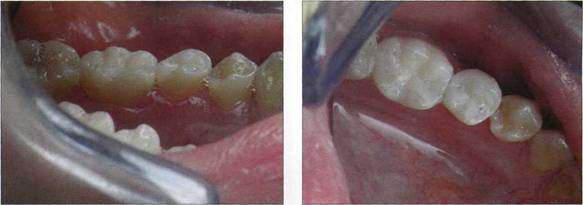

Пациентке 21 год, обратилась в клинику терапевтической стоматологии сжалобами на задержку пищи в межзубном промежутке, воспаление десневого сосочка в области 45, 46, эстетическое несовершенство пломб.

При объективном обследовании отмечается на жевательных и контактных поверхностях 45, 46 наличие пломб, не соответсвующих по цвету и форме естественным тканям коронок зубов, их усадка, неправильно сформированный контактный пункт.

Рис. 712. Исходная клиническая ситуация

Рис. 719. Конечный результат терапевтического лечения 45, 46 зубов

Конечный результат терапевтического лечения 45, 46 зубов.